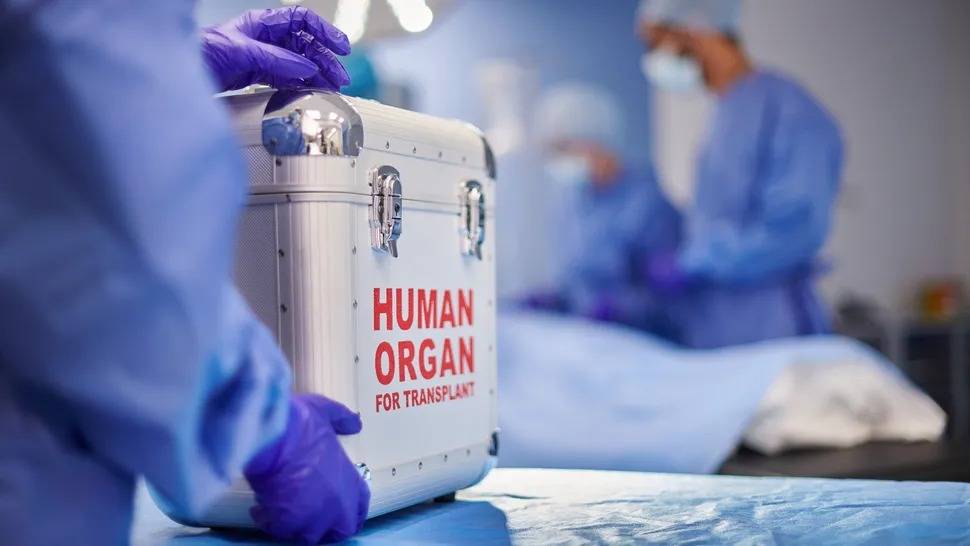

مزرعة مخبرية أمريكية تبيع أعضاء حيوانية للبشر

خلف سياج عالٍ في واد أخضر، يربّي ديفيد اياريس وفريقه خنازير معدلة وراثياً لبيع أعضائها لمرضى بشر بحاجة إلى عمليات زرع، لقاء ما يصل إلى مليون دولار. وتشهد الأبحاث المتعلقة بزرع الأعضاء الحيوانية للبشر المعروفة بالطعوم المغايرة Xenotransplantation، تقدماً سريعاً في الولايات المتحدة....